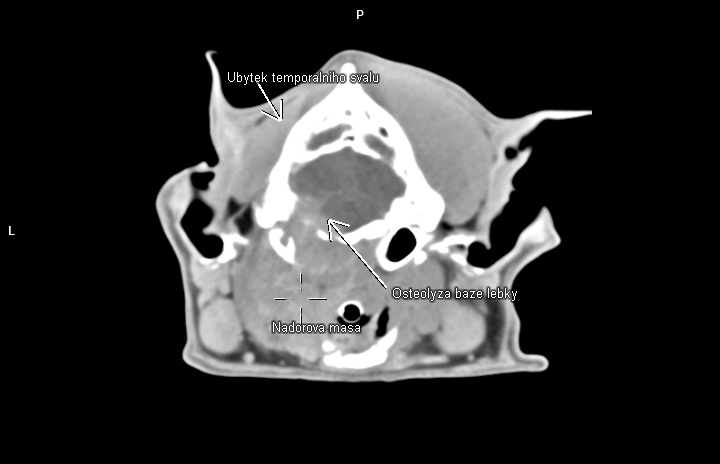

Nedílnou součástí diagnostiky ve veterinární onkologii se tak stává CT vyšetření. Velká spirální CT spolu s použitím kontrastní látky nám umožňují velmi detailní zobrazení i hlubokých struktur těla, stav okolních měkkých tkání, průběh velkých cév v bezprostředním okolí a přítomnost metastáz. Lze pak mnohem přesněji cíleně odebrat bioptické či cytologické vzorky z patologické tkáně, určit operabilnost nádoru a v případě nálezu metastatického rozsevu zvážit další postup (chemoterapie, ozařování atp.)

Jednou z oblastí, které na klinice Medipet nejčastěji pomocí computerové tomografie vyšetřujeme, je hlava a krk.

Tuto část těla postihují samozřejmě jak nezhoubné, tak často i velmi zhoubné novotvary, se špatnou prognózou.

Mezi nejčastější nálezy patří:

• nádory kostí lebky a čelistí,